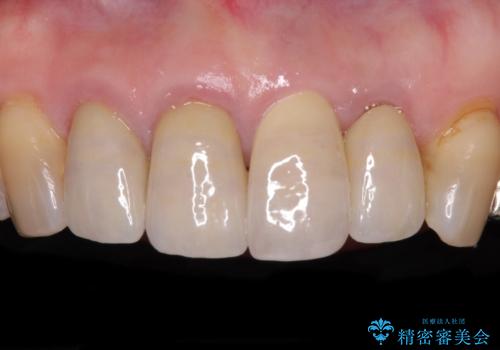

クラウンがすぐに外れてしまう 歯冠長延長術を用いた補綴治療

- 奥歯のかぶせものが頻繁に脱離することを気にされて来院された患者様です。

歯の高さが低く、かぶせものを安定して維持させることができないため、歯冠長延長術により歯の高さを増大させた上で、オールセラミッククラウンにて補綴することとしました。

歯の高さが増したことで、かぶせものが外れにくくなったことはもちろん、今まで無理と言われていたセラミッククラウンも装着でき、さらには歯間部の清掃性も向上したため、患者様には大変満足していただけました。